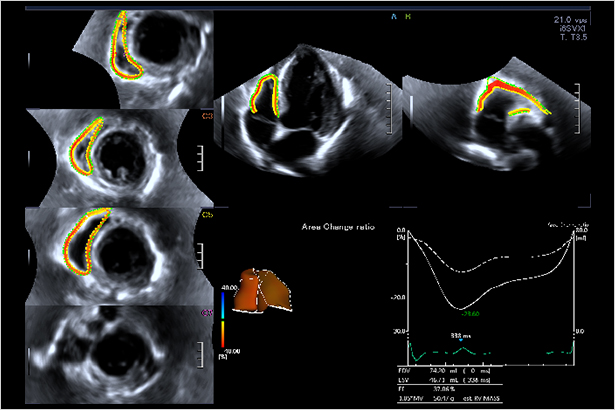

構建右心室專有分析模型,將其分為流入道,流出道及心尖部,從三維層面評價復雜的右心室心肌運動。除容積及射血分數外,還可以獲取右室整體及 7 節段應變,全面評估右室心肌運動。

心臟實時3D成像讓Aplio i900可以對心臟的四個房室進行成像和定量。